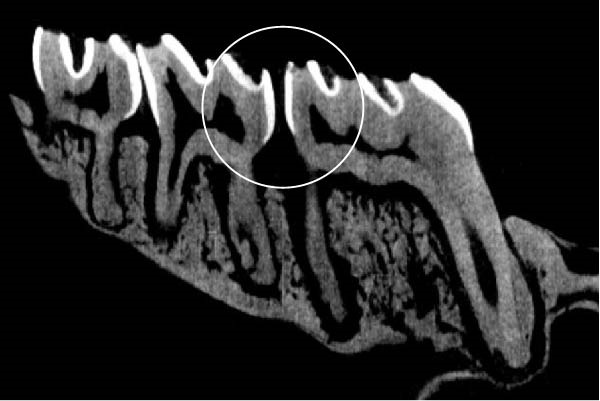

Figure 3 shows the micro‐CT images of OTM in some subgroups.

Figure 3Micro‐CT analysis of OTM after 21 and 40 days: (A) orthodontic treatment/CE injection/stress (chronic); (B) orthodontic treatment/CE injection/stress (acute); (C) orthodontic treatment/stress (chronic); (D) orthodontic treatment/stress (acute); (E) no orthodontic treatment/CE injection/stress (chronic); (F) no orthodontic treatment/CE injection/stress (acute); (G) no orthodontic treatment/no drug (chronic); (H) no orthodontic treatment/no drug (acute).(A)(B)(C)(D)(E)(F)(G)(H)